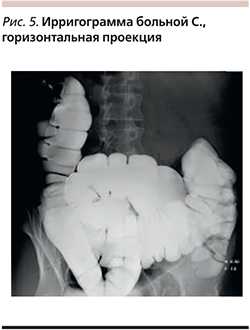

Наиболее информативным методом диагностики аномалий развития и положения толстой кишки является рентгенологический. Исследование позволяет сразу же определить положение толстой кишки в брюшной полости, форму и размеры всех ее отделов, подвижность при проведении исследования в положении больного стоя и лежа. Следующие клинические примеры продемонстрируют диагностическую ценность данного метода диагностики.

Пациентка С. 34 лет обратилась с жалобами на боли в мезогастрии, в нижних отделах живота, дипареунию, вздутие живота. Осмотрена гинекологом - без органической патологии. При ирригоскопии (рис. 5) толстая кишка удлинена за счет сигмовидной кишки, также удлинена поперечно-ободочная кишка, которая имеет дополнительные изгибы в области печеночного и селезеночного углов, центральная часть поперечно-ободочной кишки расположена над входом в малый таз.